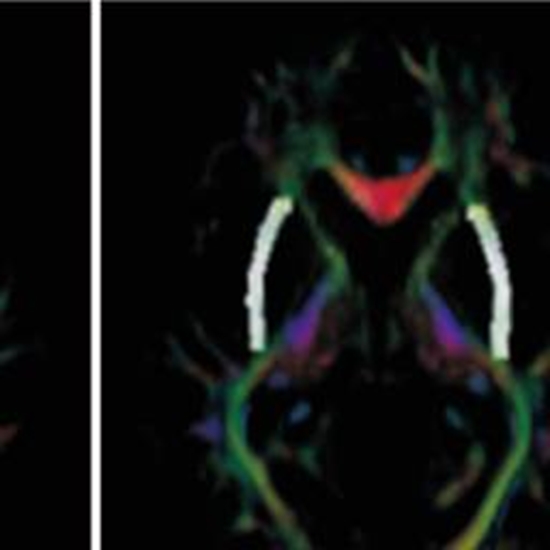

Age dependent brain subcortical white and gray matter disruptions in patients with posttraumatic stress disorder

Posttraumatic stress disorder (PTSD) is a psychiatric condition that can develop after experiencing a traumatic event, and it is associated with a range of functional and structural brain abnormalities. This study aimed to investigate age-related differences in subcortical gray and white matter in veterans with PTSD. This study recruited 44 patients with PTSD and 48 healthy controls. Participants were divided into two age groups to evaluate structural magnetic resonance imaging analysis. The results showed that individuals with PTSD had significantly smaller subcortical gray matter volumes, including the bilateral thalamus, hippocampus, amygdala, left pallidum, and right accumbens-area (P<0.05). Diffusion tensor imaging analyses revealed lower fractional anisotropy in several white matter structures, including the anterior limb of the internal capsule, anterior corona radiata, and cingulum in both hemispheres (P<0.05). Additionally, the mean diffusivity was higher in the anterior limb of the internal capsule, anterior corona radiata and the right external capsule (P<0.05). A comparative analysis between two age groups, over 50 and under 50 years old, showed that younger PTSD patients had a reduction in volume and abnormality in the corresponding white matter in more regions compared to the control group. These findings suggest that PTSD is associated with significant structural alterations in the brain, which may contribute to the pathophysiology of the disorder. So, patient age is an effective factor in exposure to traumatic events and an older age is continuously associated with a worsening traumatic brain injury outcome.